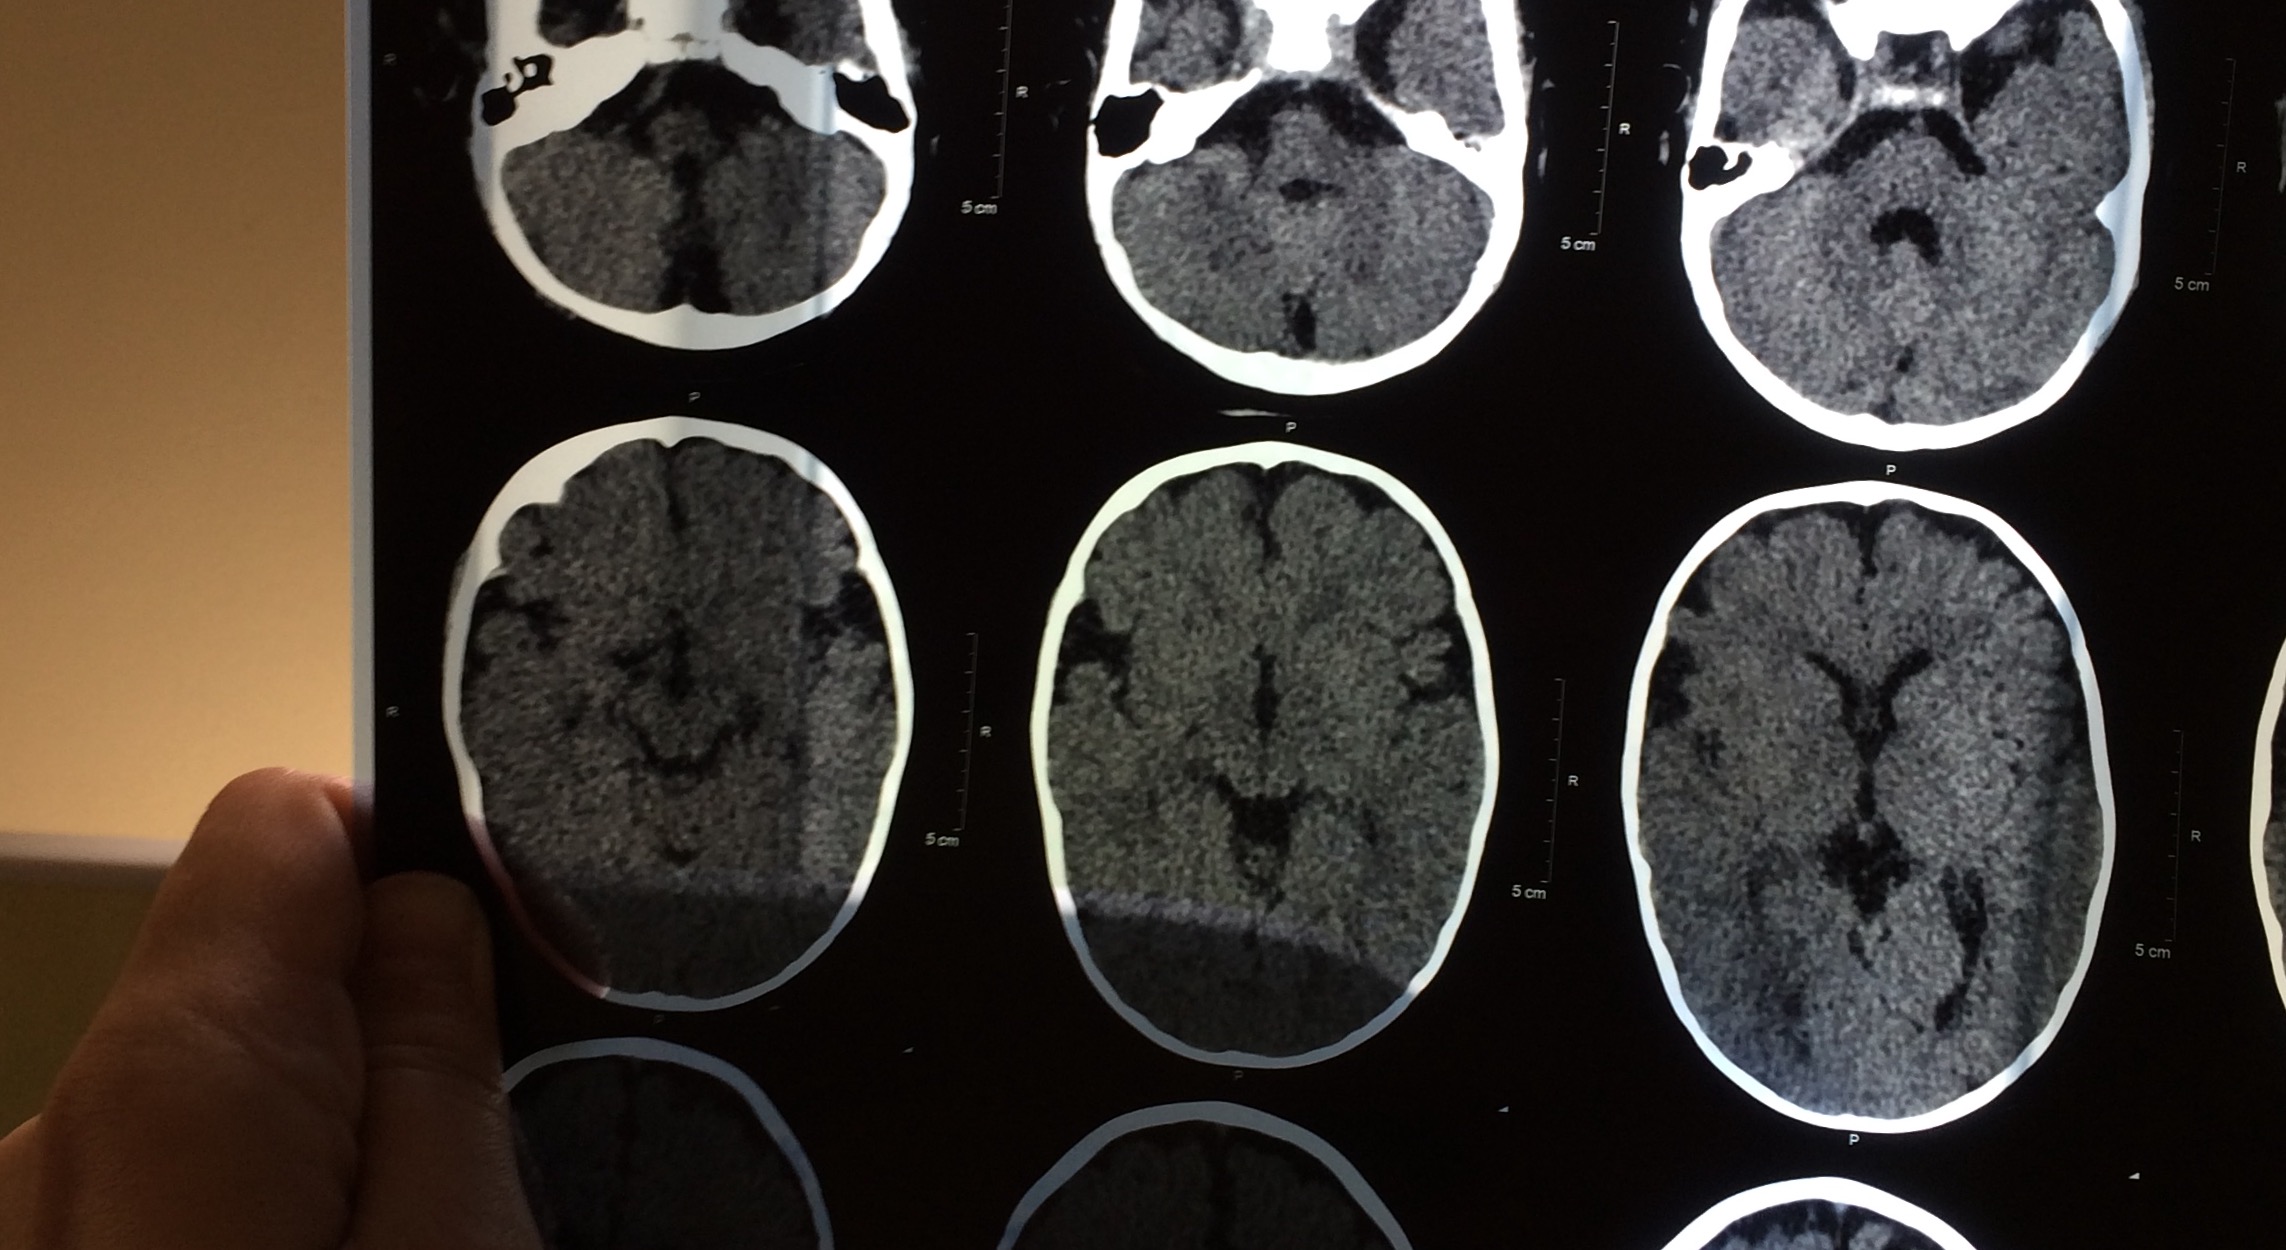

Добрый день! Сыну 7 мес . Родился на 37 неделе путём кесарева сечения. Я на последних неделях беременности 3 раза перенесла орви. Ребёнок родился с тяжёлой двусторонней пневмонией со всеми вытекающими. Был в медикаментозной коме. 12 дней на ивл. За этот период 2 раза были судороги. Реаниматологи сказали что метаболические. До месяца были на отделении опн. Выписаны домой в удовлетворительном состоянии. Наблюдались неврологом по месту жительства. ППЦНС. Пили Пантогам и 2 курса массажа. В 6 месяцев на фоне орви и субфебрильной температуры появились судороги. Фокальные. До 6-8 серий в сутки. Серия по 8-29 приступов. Длятся серии от 1 до 11 минут. Три невролога нас смотрели и без ээг и других методов обследования назначали депакин. Мы все таки добились кт и ээг. На кт-энцефалодисплазия. Похоже, что ещё при рождении все это было. Сейчас принимаем кеппру и депакин. Тут нам собираются только снять приступы, а дальше- сами.

Хочу у Вас проконсультироваться. Мы можем приехать к Вам? Что для этого надо? Какие прогнозы при таком диагнозе. Симптоматическая эпилепсия на фоне энцефалодисплазии.

IMG_5738.JPG

IMG_5737.JPG

IMG_5736.JPG